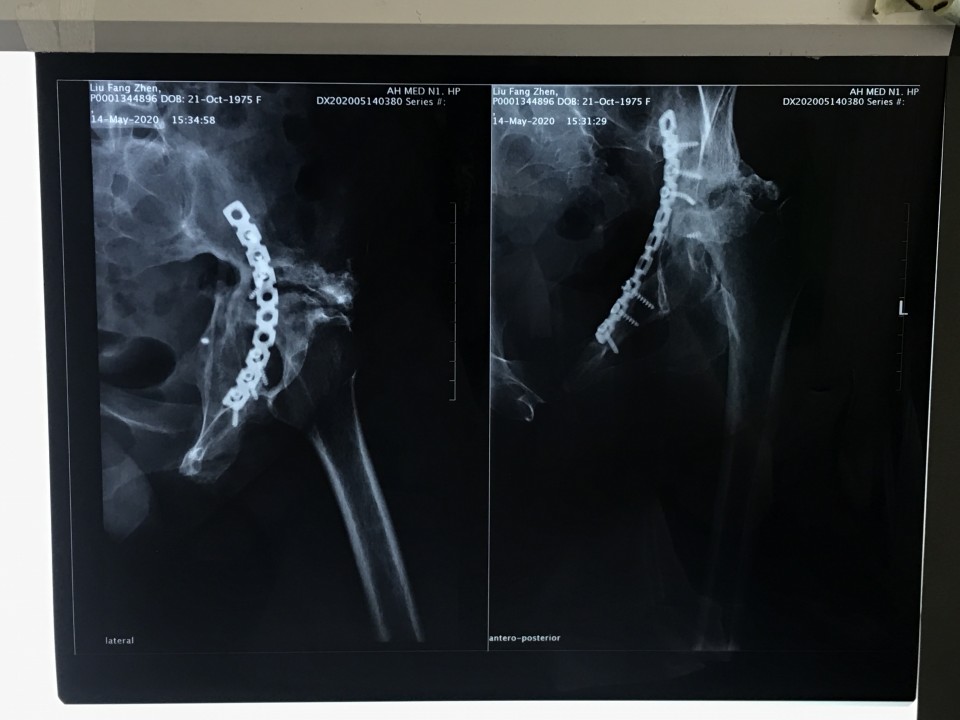

一位44岁女性患者因“左侧骨盆骨折术后疼痛伴渗液8年”入院。患者8年前因左侧骨盆骨折请上海专家行手术治疗,术后恢复不佳,髋关节感染,当地医生将部分钢板取出,残留的钢板因风险极大未予以处理。由于手术不彻底,伤口继续流脓,股骨头坏死,关节疼痛严重。因为手术风险极大,失败率高,多家医院拒收,患者慕名来到我院关节与显微修复外科胡孔足主任专家门诊,胡主任综合考虑各方因素以及现阶段我院的诊疗技术,将患者收治入院予以手术。术前结合患者病史,体检及辅助检查,反复讨论,制定了精细的手术方案,于6月10日,成功行一期手术,取出感染发炎的钢板,植入抗生素占位器。因为钢板和血管神经紧紧粘连在一起,稍有不注意就可能导致大出血,瘫痪、心跳骤停等严重后果。术后培养提示为MRSA,经过两个月规范抗感染治疗,培养提示阴性,未见细菌,感染消失。8月12日,胡主任顺利完成二期手术,“左侧全髋关节置换术”,目前手术后4天,患者已经能够扶拐下地行走,恢复良好,不久将康复出院。

髋关节内植物术后感染是一个破坏性的并发症, 给患者精神上造成很大痛苦, 经济上造成很大损失, 给医生也造成很大压力, 以往称作灾难性的并发症。但是, 随着对其认识的增加、治疗方法的改进, 现在治疗效果明显改进。虽然有很多治疗方法, 但是其中取出原来内植物彻底清创, 使用临时占位器维持软组织张力, 为局部提供高浓度抗生素, 待感染控制后再行第二期手术的方法, 是目前公认的的“金标准”,疗效满意。